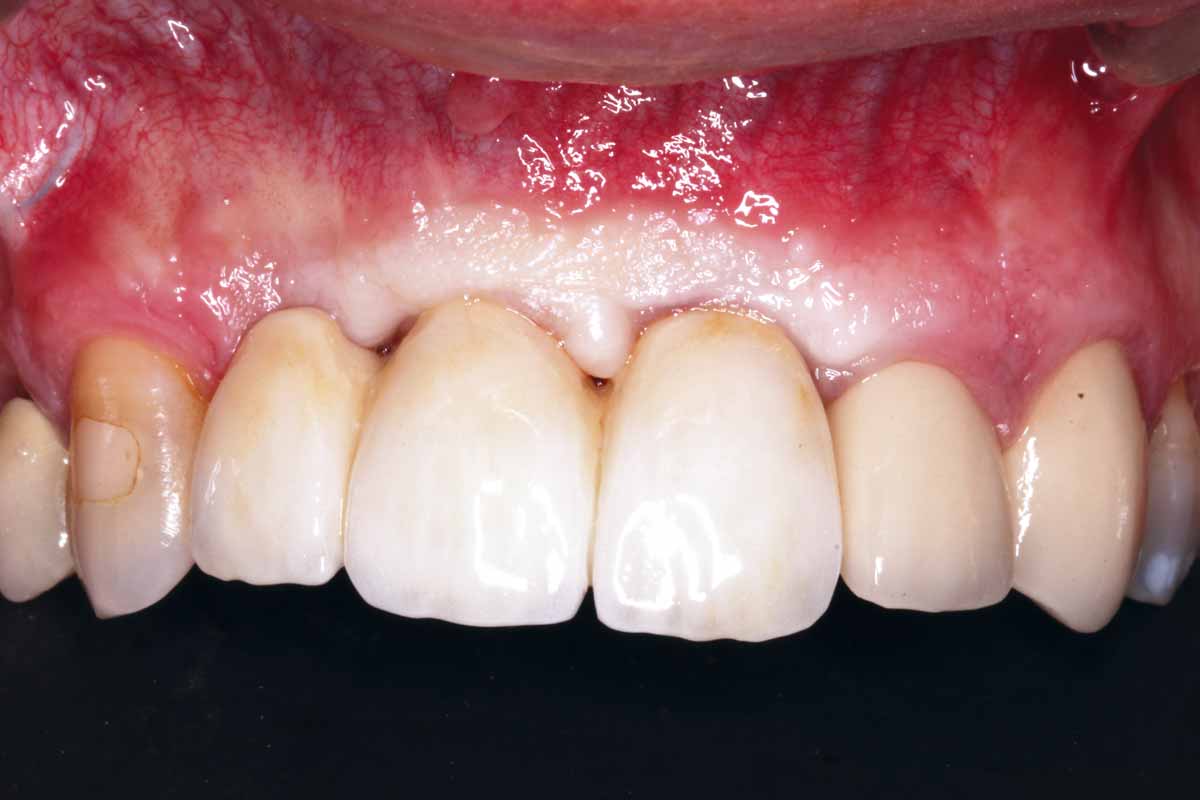

27/27 - Final clinical outcome

GBR and soft tissue augmentation with cerabone® and mucoderm® - H. Maghaireh & V. Ivancheva